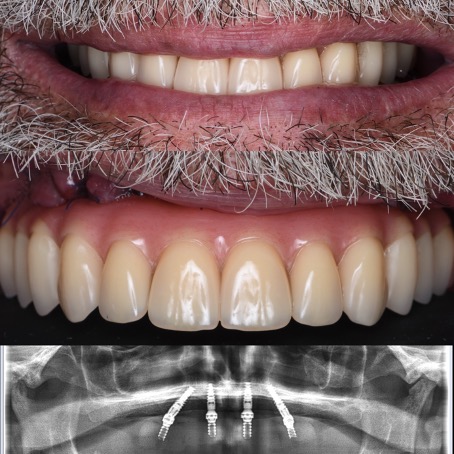

All-on-4®

Édentation totale de la mâchoire – restauration complète fixe avec des implants dentaires

Avant

Après

Selon les techniques modernes de mise en charge immédiate pour les patients édentée, nous avons la possibilité, dans la plupart des cas, d’offrir des dents fixes aux patients dans la journée.

Le protocole All-on-4® permet de réaliser immédiatement une prothèse fixe avec seulement quatre implants par mâchoire. Les implants du fond sont mis en place avec une inclinaison de 30 à 45 degrés, dans les cas où des dents encore présentes devraient être extraites le tout est fait pendant la même opération, la journée se termine pour le patient avec l’installation des dents fixes dans le 90% des cas. Une prothèse définitive sera réalisée environ 4 mois plus tard.